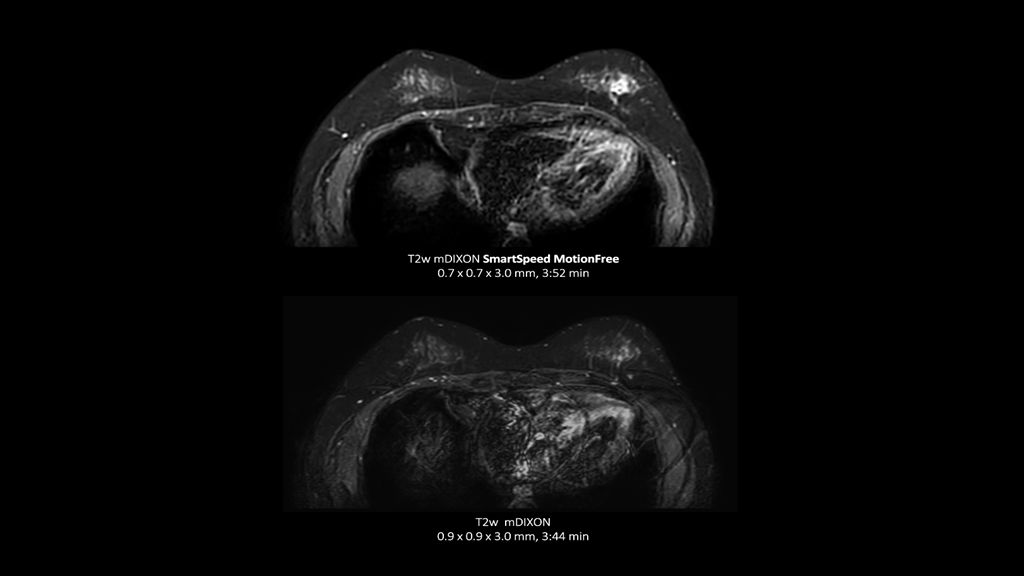

Philips - SmartSpeed Precise- Breast NMRF445C - Philips